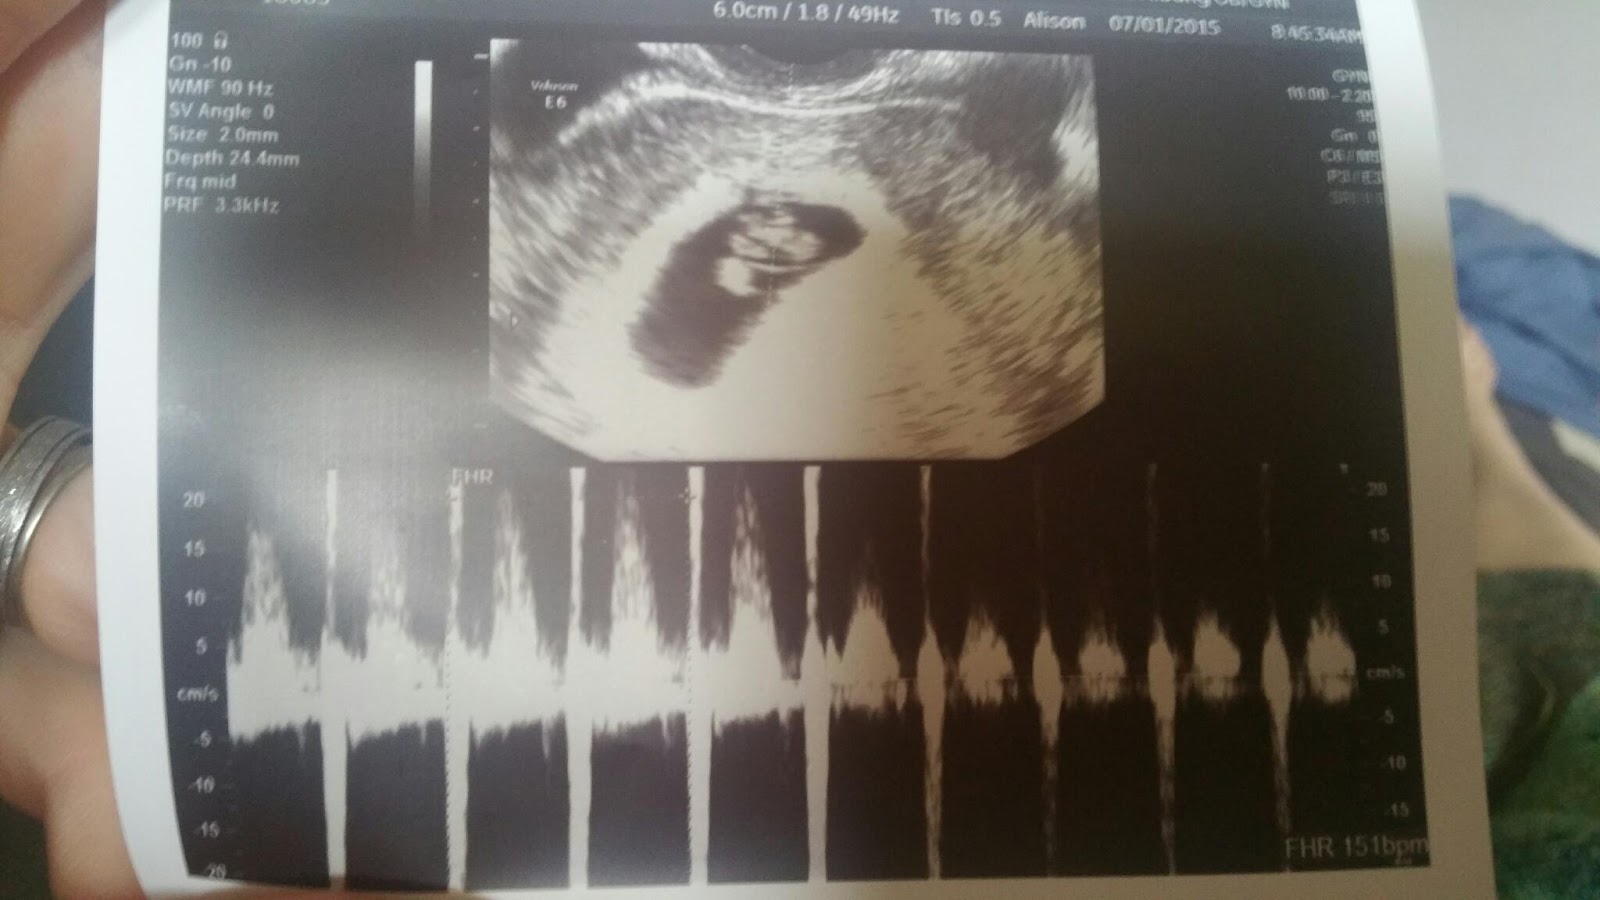

• Our sweet bean :) at 8 weeks 5 days

Wonder if it a boy and girl. I hear if heart rate is over 140 it's a girl and under 140 it's a boy @mswatters

This is my first post, but I am due 2/5/16 with my first little one. Heart rate was 167, and I'm 9w2d right now. US was taken at 8w4d